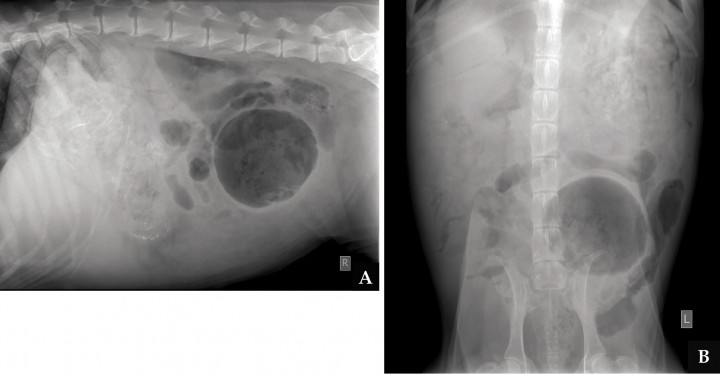

En las radiografías torácicas no se observó ninguna alteración evidente. En las radiografías de la cavidad abdominal (Figs. 2A y 2B) se apreció una pérdida de visualización de serosas de forma generalizada, más acentuada en la zona ventral derecha, así como presencia de gas libre. En la zona caudal izquierda se observó una estructura cavitaria con bordes bien definidos, de aproximadamente la longitud de tres cuerpos vertebrales lumbares (flechas de las Figs. 2A y 2B), que desplazaba algunas asas de intestino delgado hacia dorsal y craneal, y el colon descendente hacia la izquierda. En el interior de la estructura cavitaria también se apreciaba una opacidad tejido blando con áreas radiotransparentes.

<p>Mismas imágenes que la Fig 1. En ambas imágenes se aprecia pérdida de visualización de las serosas y presencia de gas libre en la zona ventral derecha. En abdomen caudal se observa una estructura cavitaria con bordes bien definidos (flechas) que desplaza dorsal y ventralmente a asas de intestino delgado y hacia la izquierda al colon. El estómago se encuentra distendido y con contenido heterogéneo, con cuerpos extraños de opacidad hueso (asterisco).</p>

Mismas imágenes que la Fig 1. En ambas imágenes se aprecia pérdida de visualización de las serosas y presencia de gas libre en la zona ventral derecha. En abdomen caudal se observa una estructura cavitaria con bordes bien definidos (flechas) que desplaza dorsal y ventralmente a asas de intestino delgado y hacia la izquierda al colon. El estómago se encuentra distendido y con contenido heterogéneo, con cuerpos extraños de opacidad hueso (asterisco).

El hígado estaba ligeramente aumentado de tamaño, con bordes redondeados y desplazando caudalmente el eje gástrico. El estómago presentaba un contenido heterogéneo y pequeños cuerpos extraños de opacidad hueso (asterisco de las Figs. 2A y B)

Radiológicamente, los textilomas aparecen como una masa de opacidad tejido blando que puede presentar en su interior un patrón moteado de opacidad gas o en forma de espiral debido al gas atrapado entre las fibras del tejido. En este caso, en el interior de la estructura cavitaria se observó una opacidad tejido blando con pequeñas áreas radiotransparentes, compatible con las gasas. Ecográficamente, la retención de gasas quirúrgicas puede visualizarse como una masa hipoecogénica con áreas hiperecógenas que, en ocasiones, pueden producir sombra acústica.